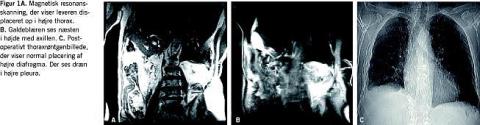

til observation på en intensivafdeling med henblik på kon-servativ behandling af et levertraume. Inden for det første døgn faldt hæmoglobinniveauet fra 8,6 mM til 7,4 mM. Der blev indlagt pleuradræn og udtømt 2 l blod. Derefter foretoges MR-skanning med MR-angiografi for nøjere at udrede traumet herunder at afklare forholdene omkring diafragma. MR-skanningen viste leveren liggende oppe i højre thorax (Figur 1A ) med galdeblæren næsten ud for axilniveau

(Figur 1B ), og der var således en betydelig ruptur af diafragma, som ikke kunne ses på CT'en.

Ved efterfølgende akut operation fandt man en ruptur af højre diafragma fra højre thoraxvæg til vena cava. Højre lunge var næsten helt atelektatisk, og størstedelen af leveren var displaceret op i thorax. Ligamentum falciforme og ligamentum teres var strammet op pga. leverens beliggenhed. Ud for tilhæftningen af ligamenterne fandtes en læsion af leverparenkymet, 1 cm dyb og 10 cm lang. Der var let siveblødning fra diafragmas rumperede tilhæftning og ingen blødning fra leverlæsionen. Leveren kunne mobiliseres via den abdominale adgang, og diafragmarupturen blev lukket med suturer i to lag. Der blev lagt pleuradræn, og lungen udfoldedes helt. Det postoperative forløb var ukompliceret. Pleuradrænet blev fjernet på femtedagen, da en thoraxrøntgenundersøgelse viste normale forhold (Figur 1C ). Patienten blev udskrevet på 14.-dagen.